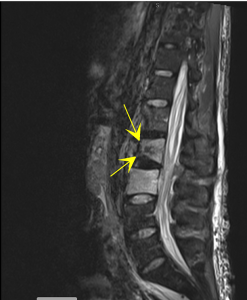

After clinical evaluation, vertebral compression fractures are diagnosed using imaging studies such as:

-

X-ray

CT scan

MRI

Bone scintigraphy

These tests also help determine whether the fracture is recent or old, which is crucial for selecting the appropriate treatment.